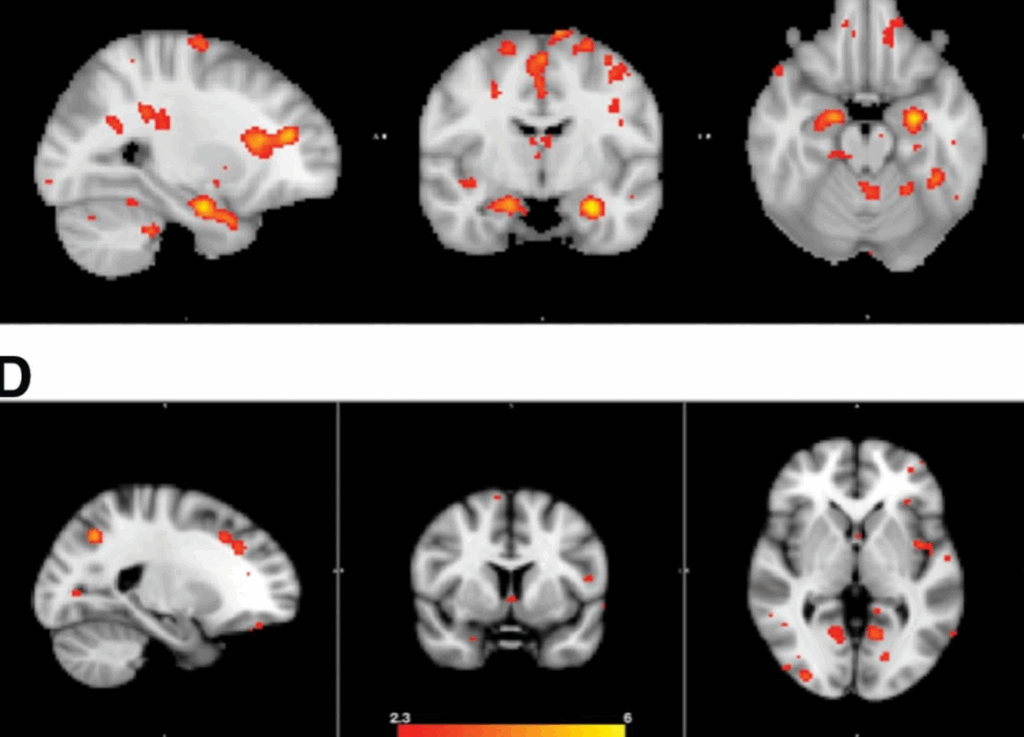

ASSOCIATION OF SERUM‐BASED PLASMALOGENS WITH NEUROIMAGING AND GENETIC VARIATION IN ALZHEIMER'S DISEASE

Published on 01 July 2019